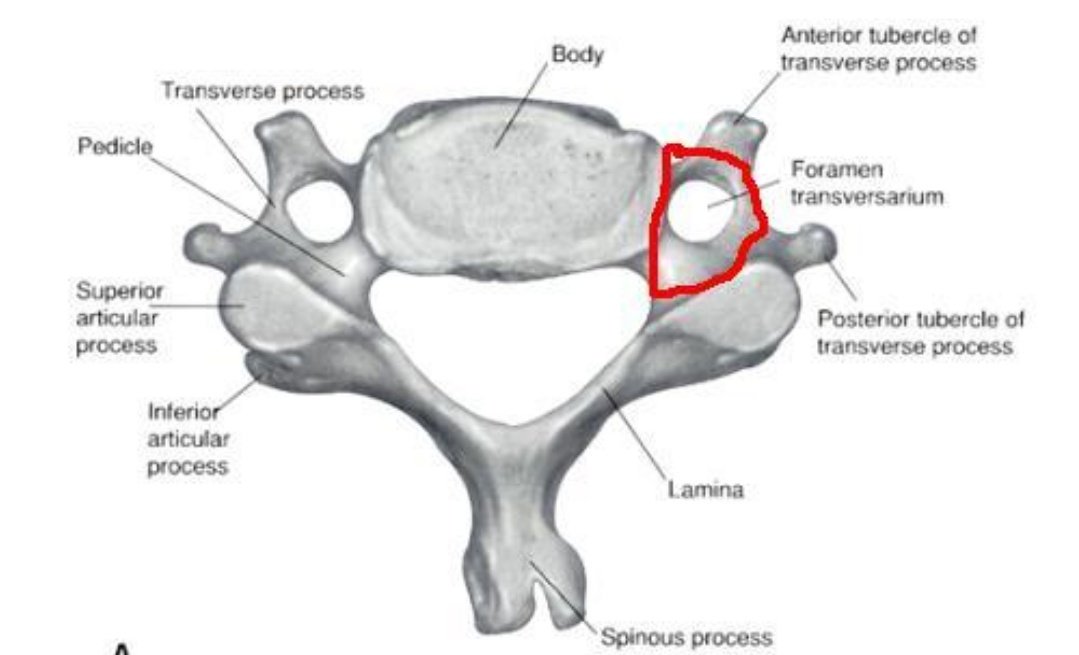

•تتميزالفقرات العنقيةبوجود فتحات تسمى

Transverse foramen=foramen transversarium

تمر فيها شرايين و أوردة و بعض الأعصاب.